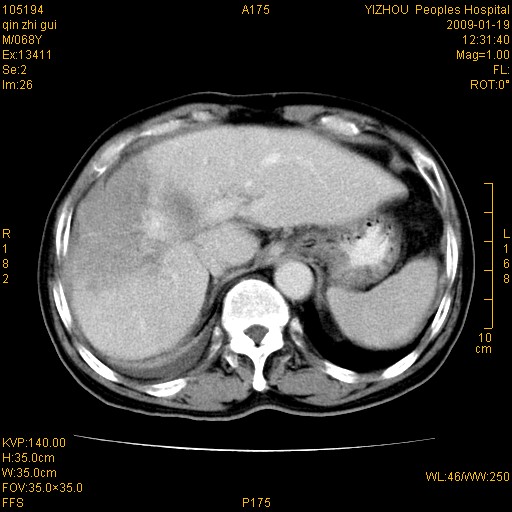

以下是引用随光逐影在2009-1-21 16:11:00的发言:[br]1)考虑肝右叶肝癌并肝静脉及门静脉瘤栓形成。2)肝硬化,少量腹水。3)胆囊炎。4)右侧少量胸腔积液。

病灶外缘凹凸不平,平扫低密度,增强动脉期有强化,门脉早显,静脉期及延期呈延迟强化,结合病史考虑右肝前叶巨块型肝癌可能性大,强化表现不除外胆管细胞癌